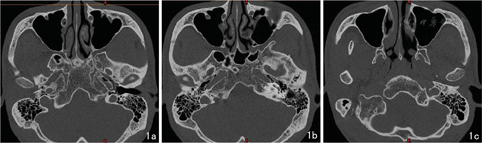

先在颞骨轴位层面准确定位解剖位置恒定的棘孔位置(图1a),作一条过棘孔中点的水平线,确定为过棘孔中点的冠状面。保持这条水平线不变,寻找面神经垂直段的起点(第二膝末端)和终点(茎乳孔层面)。在面神经垂直段起点和终点层面,分别测量面神经垂直段至棘孔及面神经至乳突的距离(图1b、图1c)。测量数据分别可以准确反映面神经前、后方向的位移改变。颞骨轴位层面上,准确定位面神经垂直段起点和终点后(图1b、图1c),在这两个层面,分别作一条过乳突最凸点的前后方向切线,测量面神经垂直段至过乳突切线的距离。这个距离可以一定程度反映面神经垂直段是否外移。